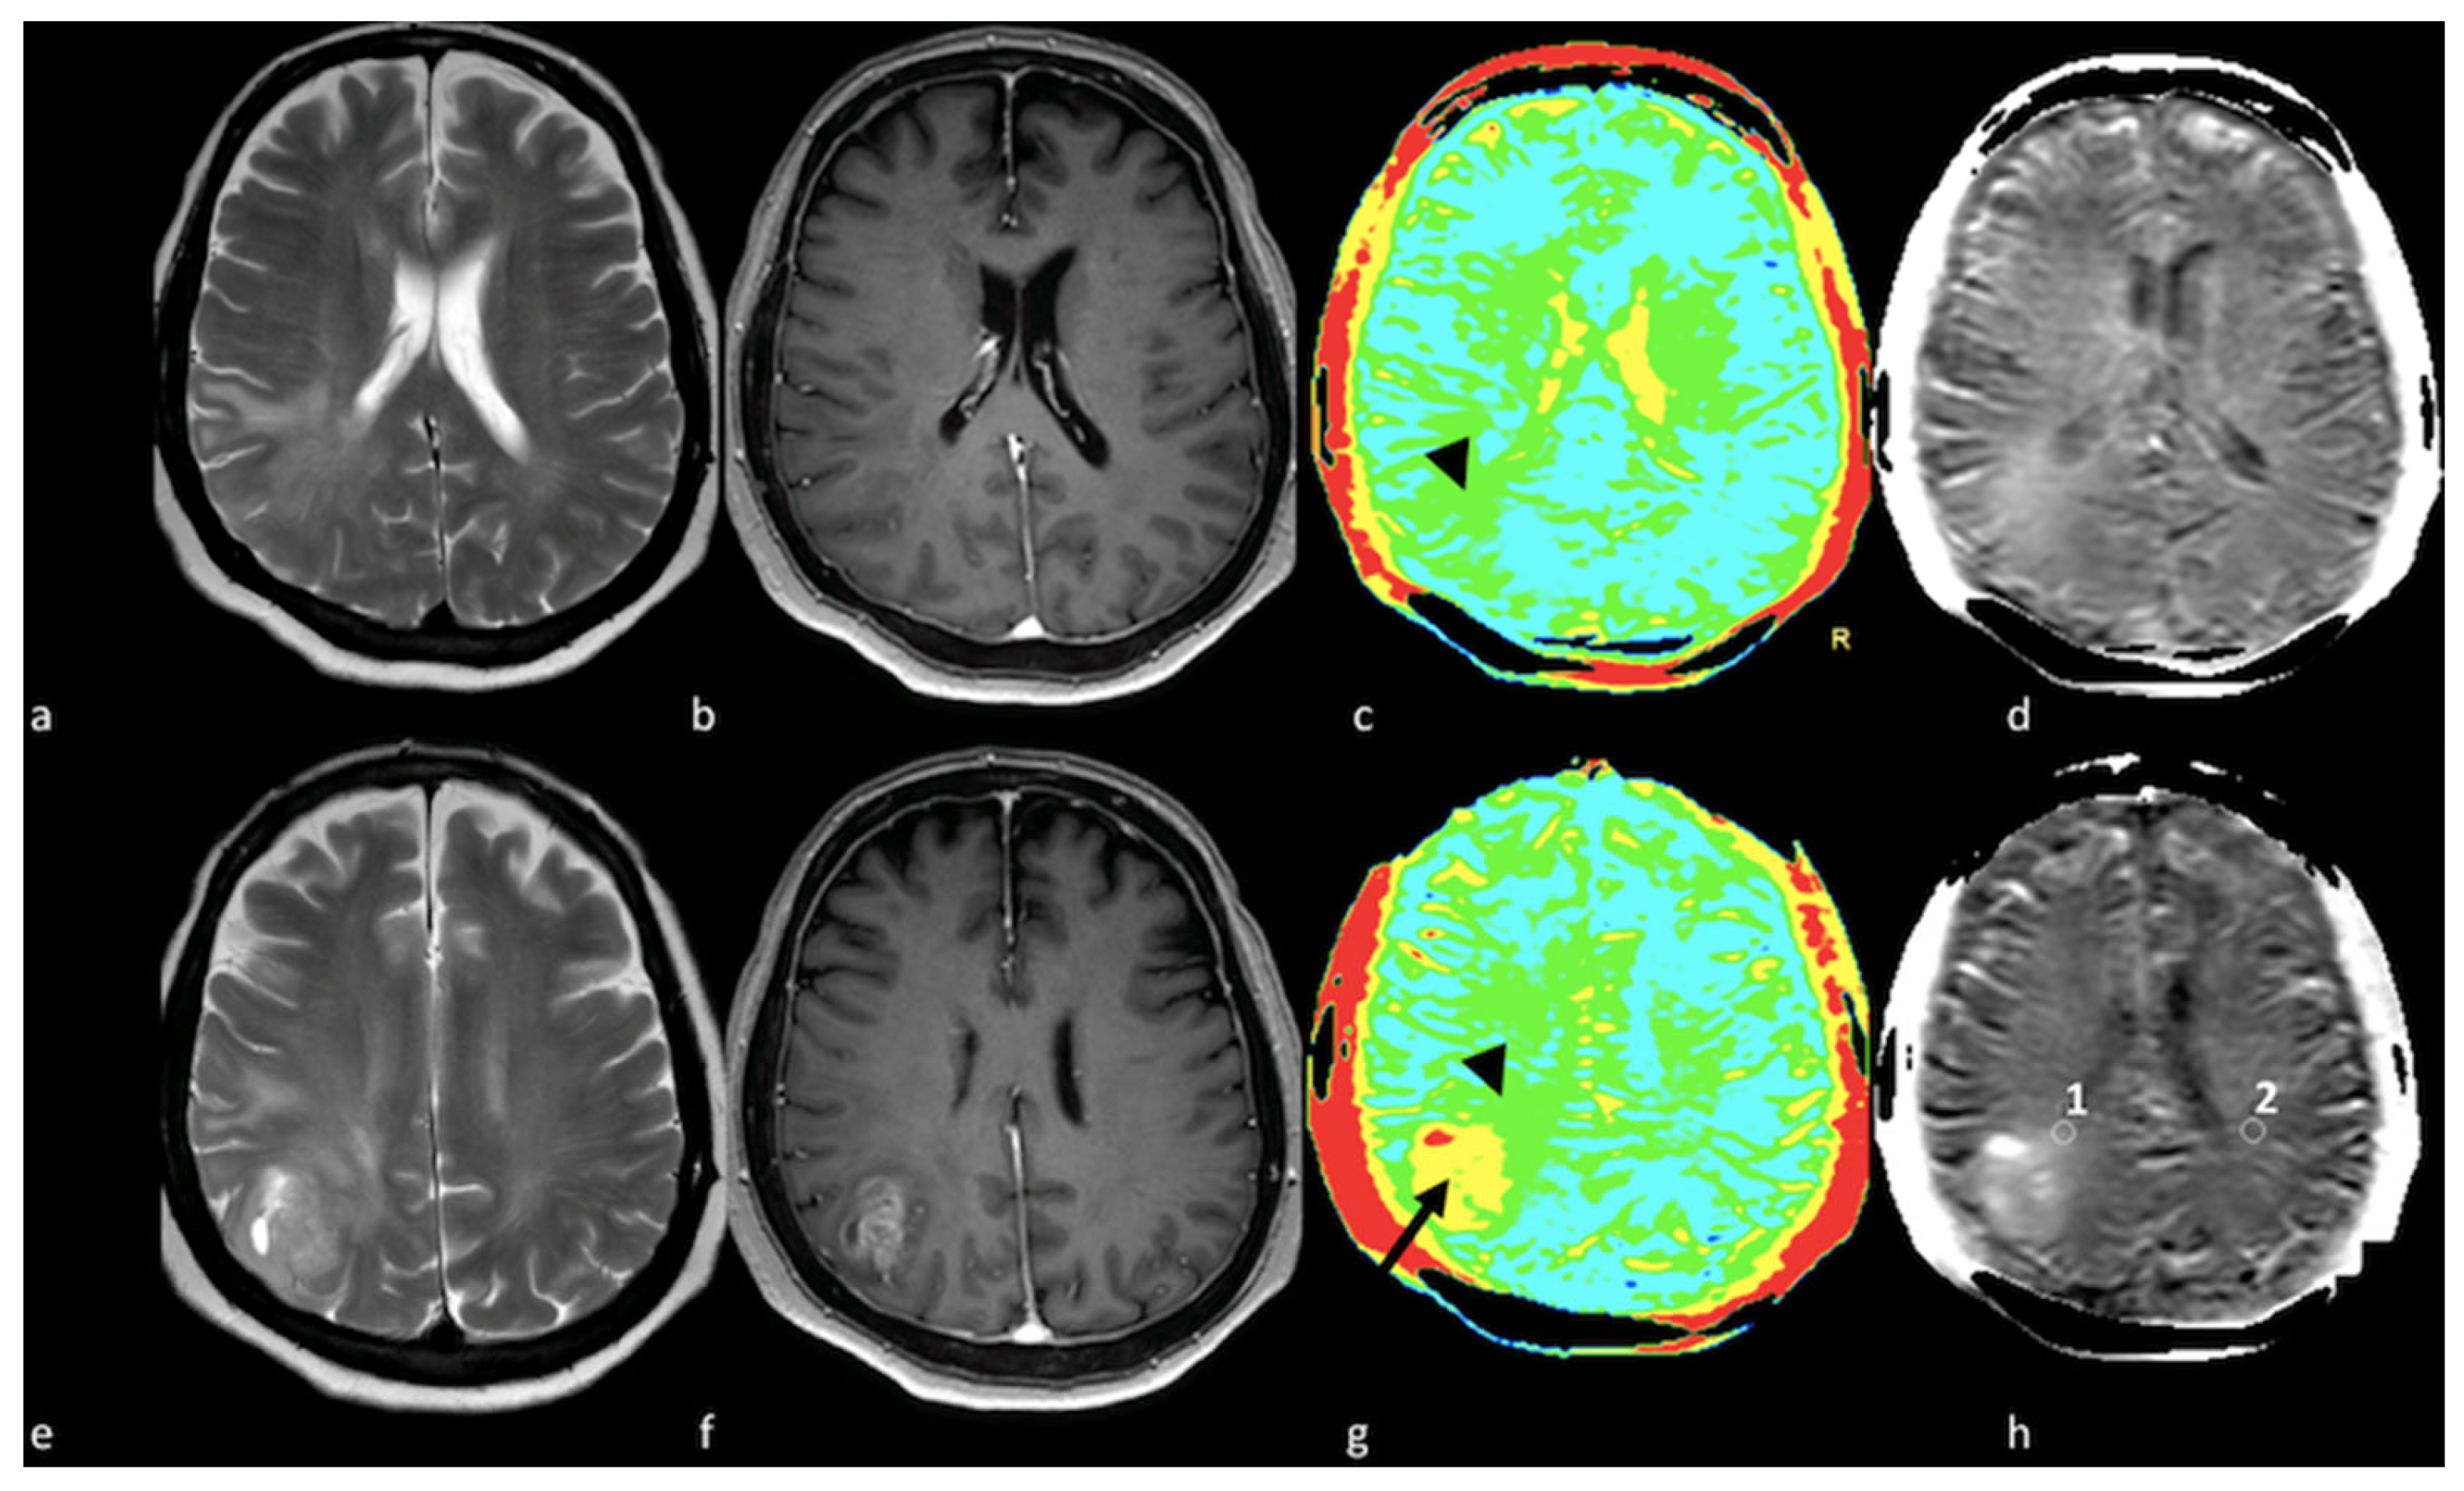

3.3.3. Arterial Spin Labeling

- Sunwoo, L.; Yun, T.J.; You, S.H.; Yoo, R.E.; Kang, K.M.; Choi, S.H.; Kim, J.H.; Sohn, C.H.; Park, S.W.; Jung, C.; et al. Differentiation of Glioblastoma from Brain Metastasis: Qualitative and Quantitative Analysis Using Arterial Spin Labeling MR Imaging. PLoS ONE 2016, 11, e0166662. [Google Scholar] [CrossRef] [PubMed]

- You, S.H.; Yun, T.J.; Choi, H.J.; Yoo, R.E.; Kang, K.M.; Choi, S.H.; Kim, J.H.; Sohn, C.H. Differentiation between primary CNS lymphoma and glioblastoma: Qualitative and quantitative analysis using arterial spin labeling MR imaging. Eur. Radiol. 2018, 28, 3801–3810. [Google Scholar] [CrossRef] [PubMed]

- Lin, L.; Xue, Y.; Duan, Q.; Sun, B.; Lin, H.; Huang, X.; Chen, X. The role of cerebral blood flow gradient in peritumoral edema for differentiation of glioblastomas from solitary metastatic lesions. Oncotarget 2016, 7, 69051–69059. [Google Scholar] [CrossRef] [PubMed]